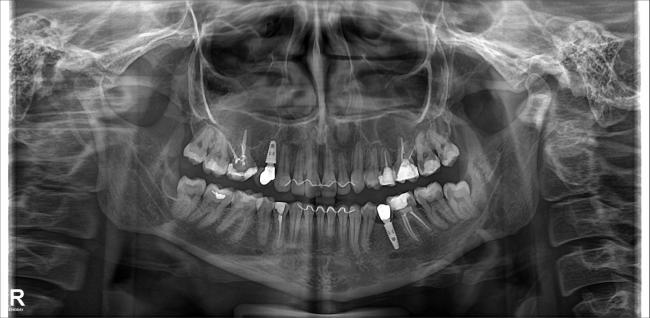

Radiografia Panorâmica

Obtenha uma visão ampla e detalhada da estrutura bucal para auxiliar em planejamentos ortodônticos.